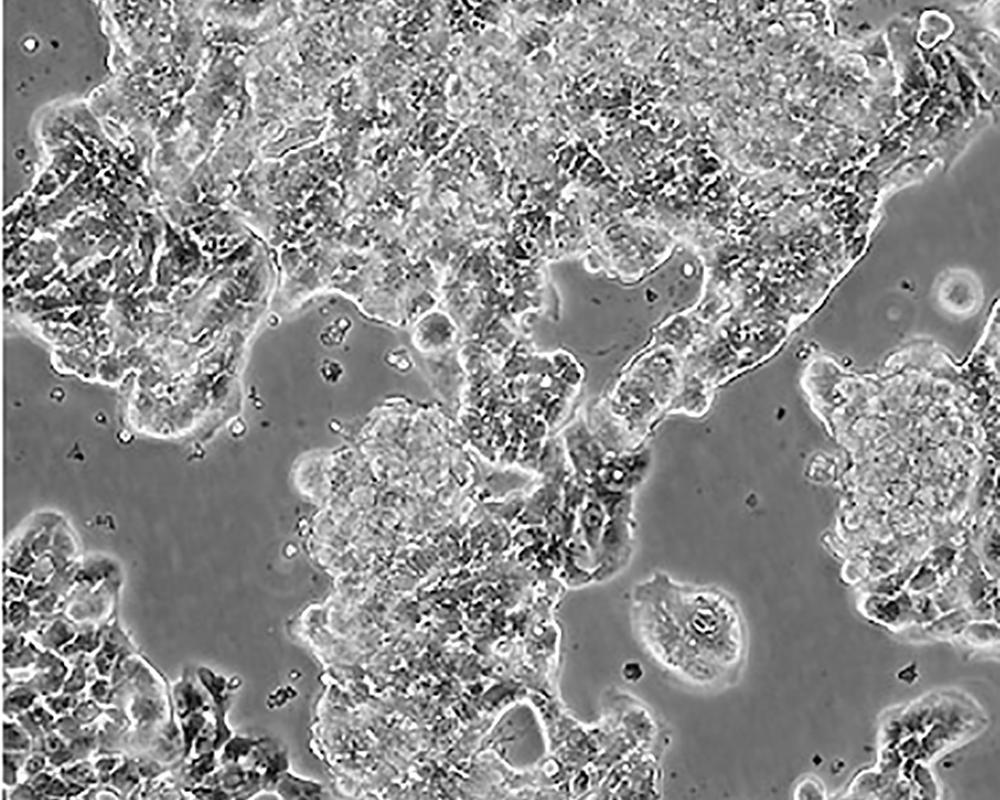

生長(zhǎng)特性 adherent

形態(tài)特征 epithelial

細(xì)胞描述 該細(xì)胞產(chǎn)生高水平的黏液素MUC-1 mRNA,低水平的MUC-2 mRNA,但不表達(dá)MUC-3基因;表達(dá)雌激素受體。